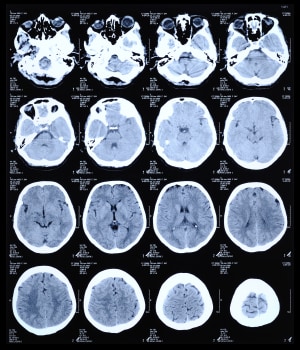

CT is one of the two technologies that utilize ionizing radiation to create a picture of what is going on inside the body. At its simplest, a CT scan is an x-ray slice of the body. Slices are repeated along the area of interest, although for performance reasons multiple slice transmitters/receivers are typically grouped next to each other. The body can also be moved during exposure in order to create a “spiral” image that can be unwound into slices or a 3D view (see Figure 1).

Figure 1: CT scan of the human brain.